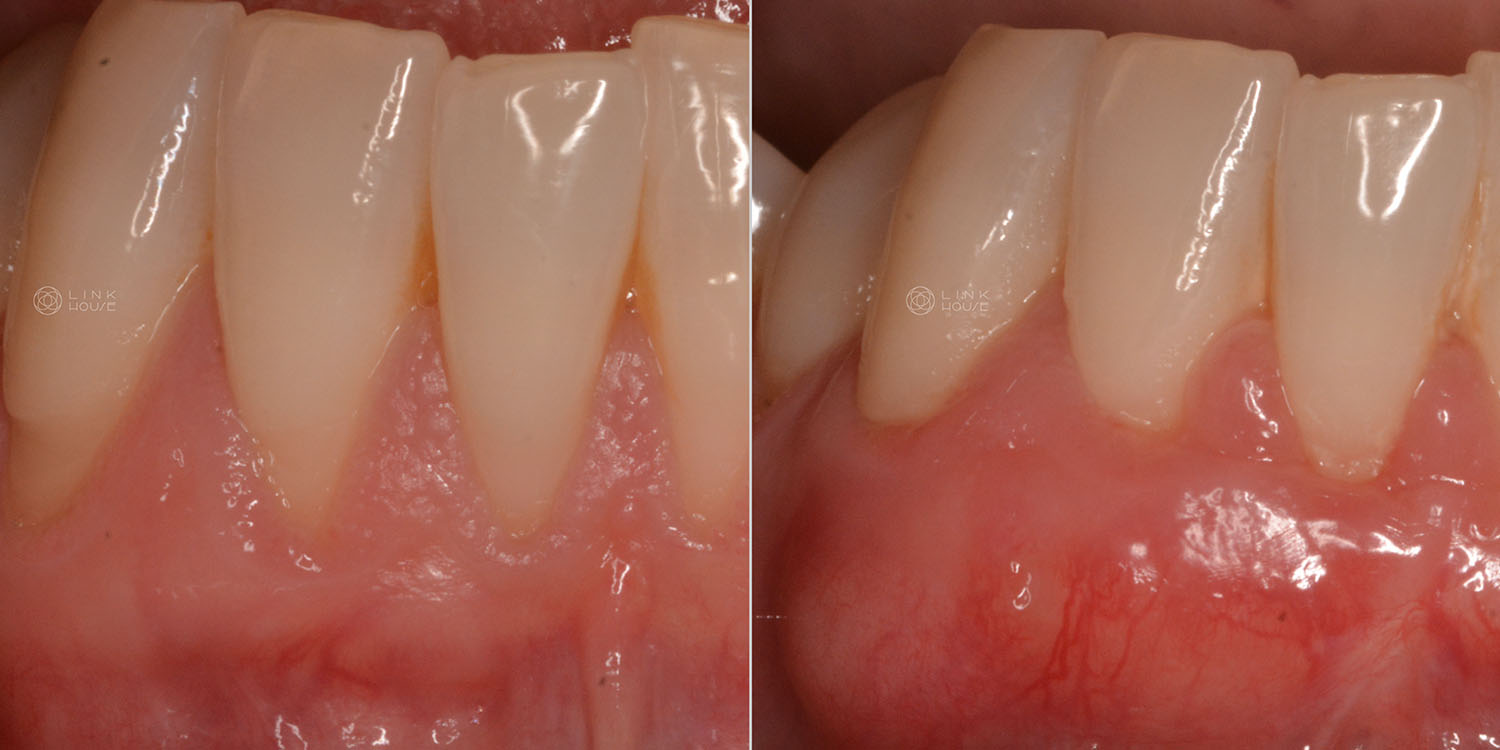

Gum Recession

Gum recession is when your gum tissue pulls away from your teeth, exposing the roots underneath.

It’s caused by several factors, including overzealous brushing, mouth trauma, periodontal disease, orthodontics, lip/tongue piercings and genetics.

Exposed teeth roots increase your risk of tooth decay, sensitivity and bone loss around teeth.

Gum surgery can improve thinning gums and gum recession. In some cases, a gum graft is required to cover the roots of the exposed teeth and add volume to your gums. This restores the missing gums and reduces the risk of further gum recession. Gum graft surgery can be performed on one tooth or multiple teeth.

There are many gum grafting techniques and materials available. We commonly take tissue from your palate (the roof of your mouth) and move it to the area of recession. In some cases, though, we may use a substitute grafting material.